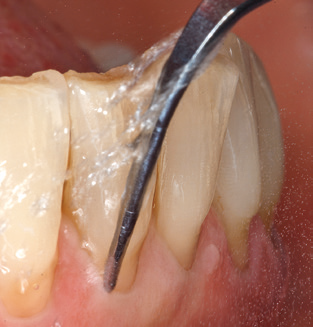

Good illumination of the working field facilitates the process considerably. The system used by the authors achieves this thanks to a 5x LED ring integrated in the handpiece. Naturally, a range of working tips for different indications is also offered. A straight, universally employable tip is the basic instrument required for machine cleaning of natural teeth (Fig. 5a and b). Curved tips, which allow access to exposed furcations, are also available for hard-to-reach areas in the posterior region (Fig. 6).

Of course, working tips for the cleaning of implant surfaces are also indispensable for SPT in patients fitted with implants. The implant cleaning attachment on the system used here is characterised by its tapered, hexagonal design. This design allows light, atraumatic penetration of the peri-implant pocket and displays a good cleaning performance (Fig. 7).